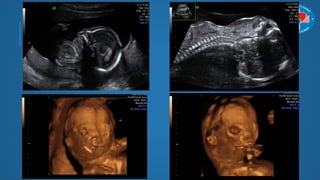

SIÊU ÂM 4D

Thực chất là hình ảnh video 3D (live-3D, 4D, 3D real time)

Chiều thứ 4 là “chiều thời gian”

Giúp quan sát đƣợc cử động trực của thai nhi trong bụng

mẹ

SIÊU ÂM 4D Thựcchất là hình ảnh video 3D (live-3D, 4D, 3D real time) Chiều thứ 4 là “chiều thời gian” Giúp quan sát đƣợc cử động trực của thai nhi trong bụng mẹ